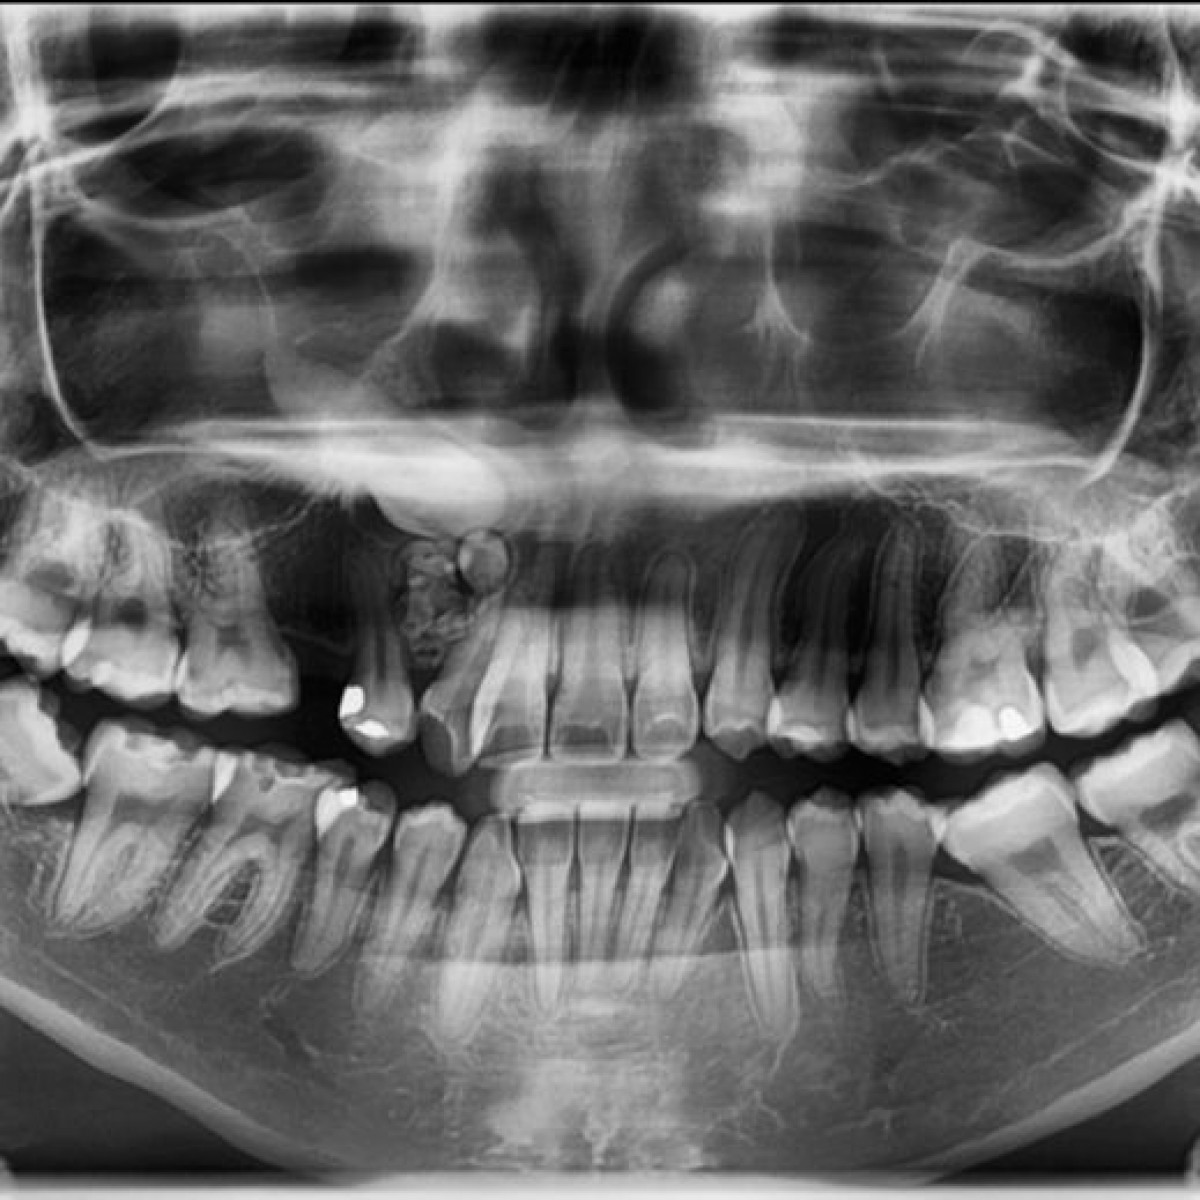

Adenoid ameloblastoma with dentinoid had been perceived as a rare odontogenic tumor with bridging histopathological features between ameloblastoma and adenomatoid odontogenic tumor. Due to the mixture of histopathological features of two separate and well-recognized entities, adenoid ameloblastoma was also regarded as a hybrid lesion. The diversity in the histopathological presentation among the cases has disaccorded the nature, behaviour, and prognosis of this pathology. Despite the literature acknowledging the histopathological diversity, categorizing all these variations into one and addressing them as a single entity was lagging till the 5th edition of the odontogenic tumor classification by the WHO was forwarded. With the establishment of the new terminology of adenoid ameloblastoma and the enlistment of its diagnostic criteria, the scientific literature has advocated updating, contributing, and redefining the various aspects of this pathology. Here, we present a case of a 34-year-old male who presented with a chief complaint of swelling in the lower front region of his jaw in the past one month. The swelling was associated with pain that was sudden in onset with a progressive increase in size. The swelling was also associated with discharge that resembled pus. A panoramic radiograph showed a mixed radiopaque and radiolucent area, extending from the distal aspect of 32 up to the distal aspect of 43. The entire cystic lining along with the growth was excised and sent for histopathological examination. Correlating clinically, the histopathological features are suggestive of adenoid ameloblastoma. Scientific literature has stood as a boon to evidence-based practice. The diagnosis for the present case report is truly an outcome of the literature-based update which helped the diagnosis of the case as a separate entity rather than as a hybrid pathology. The goal was to enhance the understanding of the lesions in terms of their clinical characteristics and diverse histopathological morphology.